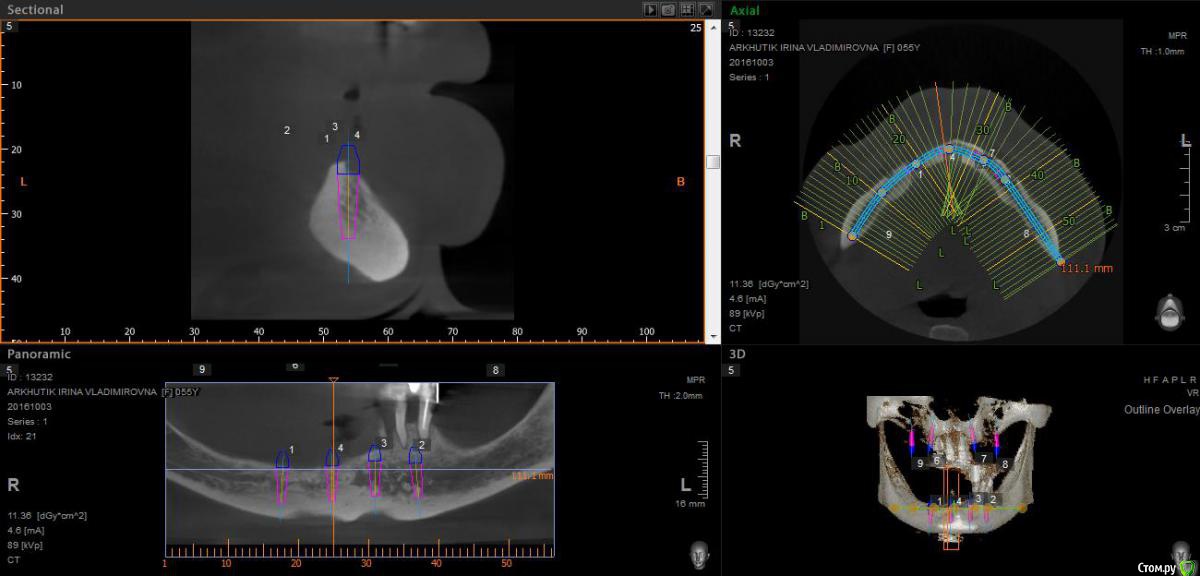

Rusty Опубликовано 5 октября, 2016 Поделиться Опубликовано 5 октября, 2016 Добрый день. К ортопеду обратилась пациентка 55-60 лет с такой ситуацией. Пришла с дочкой, дочь с мамой настаивали на несьемной конструкции, ортопед отправил на кт и вот. Не хочу планировать ей много хирургии, оцените и мой план пожалуйста и буду рад услышать советы по реабилитации пациента. По сути да) просто искал место куда есть возможность поставить, ортопед говорит тогда балка либо локаторы Ссылка на комментарий

Nazim_NV86 Опубликовано 5 октября, 2016 Поделиться Опубликовано 5 октября, 2016 На н/ч балка? Какие измерения в дист отделах? На в/ч мало четырёх. По три бы. Ссылка на комментарий

Rusty Опубликовано 5 октября, 2016 Автор Поделиться Опубликовано 5 октября, 2016 На н/ч балка? Какие измерения в дист отделах? На в/ч мало четырёх. По три бы.На н/ч балка, в дистальных отделах над каналом около 3мм. На вч условий для установки больше 4 не нашел) Ссылка на комментарий

Nazim_NV86 Опубликовано 6 октября, 2016 Поделиться Опубликовано 6 октября, 2016 Попробуйте на вч поискать ещё возможность хотя бы по Палаччи поставить. Ссылка на комментарий

Nazim_NV86 Опубликовано 6 октября, 2016 Поделиться Опубликовано 6 октября, 2016 А на низ кроме блоков больше рабочих методов не вижу. Ссылка на комментарий